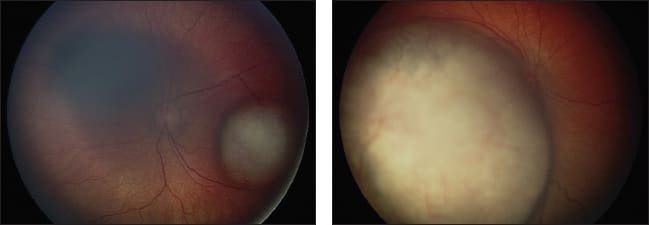

Figure 1. Left eye of a child with large macular retinoblastoma before treatment (top) and after intra-arterial melphalan and focal laser consolidation (bottom).